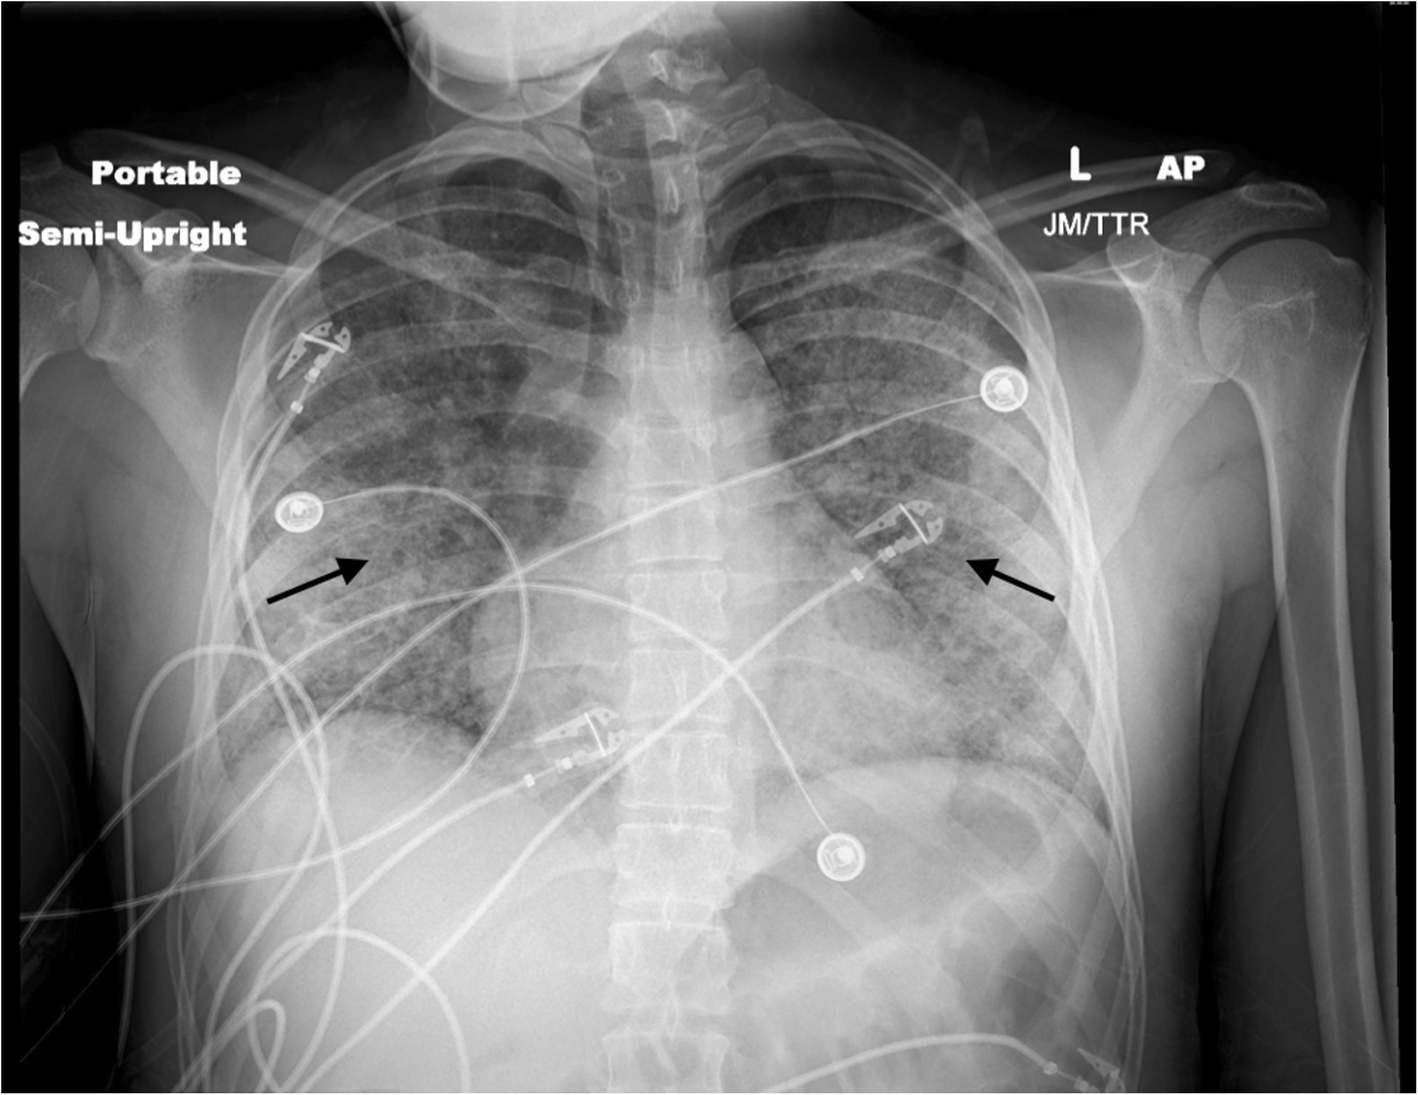

Fig. 2From: A 23-year-old man with acute lung injury after using a tetrahydrocannabinol-containing vaping device: a case reportChest x-ray demonstrating diffuse central predominant interstitial opacities (black arrows)Back to article page